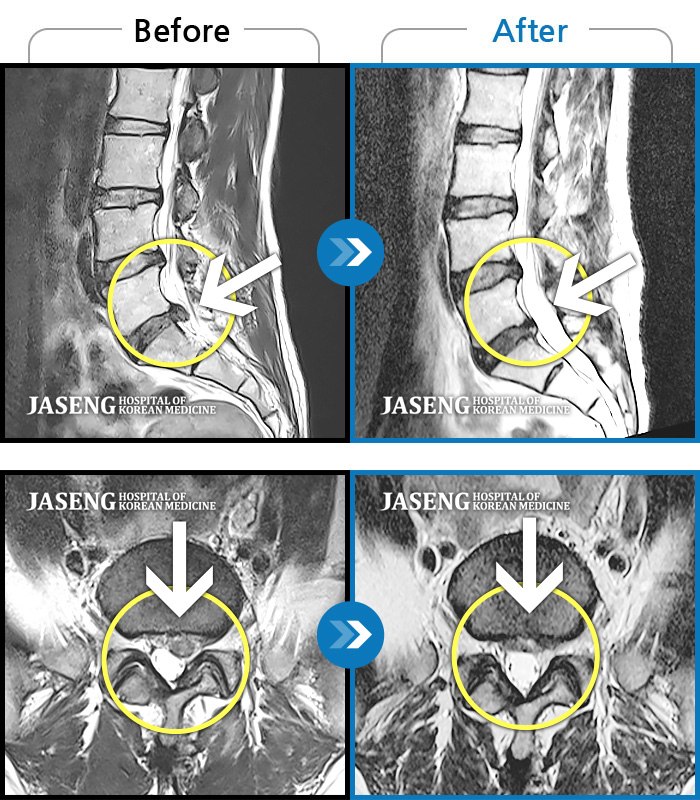

• 허리디스크

• 척추관협착증